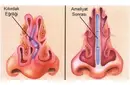

Burun Kıkırdak Eğriliği Belirtileri ve Tedavisi

Burun kıkırdak eğriliği, burun septumundaki bozuklukların neden olduğu rahatsız edici bir durumdur. Belirtileri arasında burun tıkanıklığı, baş ağrıları ve uyku apnesi yer alır. Tedavi seçenekleri, ilaçlardan cerrahi müdahalelere kadar değişir. Uzman görüşü, en uygun çözüm için önemlidir.

Burun Kıkırdak Eğriliği Belirtileri ve Tedavisi Burun kıkırdak eğriliği, burun septumunun (burun ortasındaki yapı) anormal bir şekilde eğrilmesi veya şekil bozukluğu olarak tanımlanabilir. Bu durum, bireylerin yaşam kalitesini etkileyen ve çeşitli sağlık sorunlarına yol açabilen önemli bir rahatsızlıktır. Burun kıkırdak eğriliği, genellikle doğuştan gelir, ancak travma veya yaralanmalar sonucu da gelişebilir. Burun Kıkırdak Eğriliğinin Belirtileri Burun kıkırdak eğriliği, birçok belirtiyle kendini gösterebilir. Bu belirtiler kişiden kişiye değişebilir, ancak genel olarak aşağıdaki semptomlar sıklıkla görülmektedir:

Bu belirtiler, bireyin günlük yaşamını olumsuz etkileyebilir ve bazen daha ciddi sağlık sorunlarına yol açabilir. Burun Kıkırdak Eğriliğinin Nedenleri Burun kıkırdak eğriliğinin nedenleri genellikle aşağıdaki gibi sıralanabilir:

Tanı Yöntemleri Burun kıkırdak eğriliğinin tanısı, genellikle bir kulak burun boğaz uzmanı tarafından yapılır. Tanı sürecinde kullanılan yöntemler şunlardır:

Tedavi Seçenekleri Burun kıkırdak eğriliği tedavisi, hastanın semptomlarına ve durumun ciddiyetine bağlı olarak değişiklik gösterir. Tedavi yöntemleri şunlardır:

Sonuç Burun kıkırdak eğriliği, birçok bireyi etkileyen yaygın bir durumdur. Belirtiler, yaşam kalitesini olumsuz etkileyebilir ve tedavi edilmediği takdirde daha ciddi sorunlara yol açabilir. Bu nedenle, burun kıkırdak eğriliği belirtileri yaşayan kişilerin bir uzmana başvurması önemlidir. Tedavi seçenekleri sayesinde, bireyler bu rahatsızlıktan kurtulabilir ve daha sağlıklı bir yaşam sürdürebilirler. Ek olarak, burun kıkırdak eğriliği ile ilgili daha fazla bilgi edinmek isteyen bireylerin, kulak burun boğaz uzmanları ile iletişime geçmeleri önerilmektedir. Bu uzmanlar, durumun ciddiyetini değerlendirerek en uygun tedavi yöntemini belirlemede yardımcı olabilirler. |